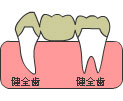

※ブリッジとは

両隣の歯を削って、真ん中にダミーの歯を置くことで歯を作る方法です。

ただ、欠損部が大きくなれば、支えている歯の負担は大きくなります。

ただ、欠損部が大きくなれば、支えている歯の負担は大きくなります。